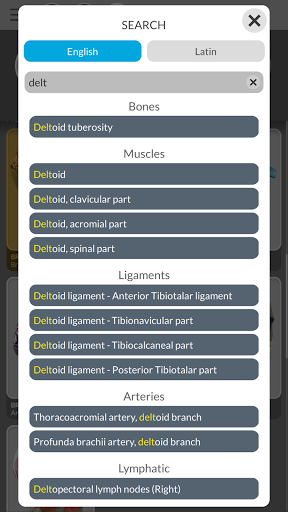

• Fonction de recherche pour trouver facilement chaque partie anatomique

MULTILINGUE

• Les termes anatomiques et l'interface utilisateur sont disponibles en 11 langues : latin, anglais, français, allemand, italien, portugais, turc, russe, espagnol, chinois, japonais et coréen

• Les termes anatomiques peuvent être affichés en deux langues simultanément